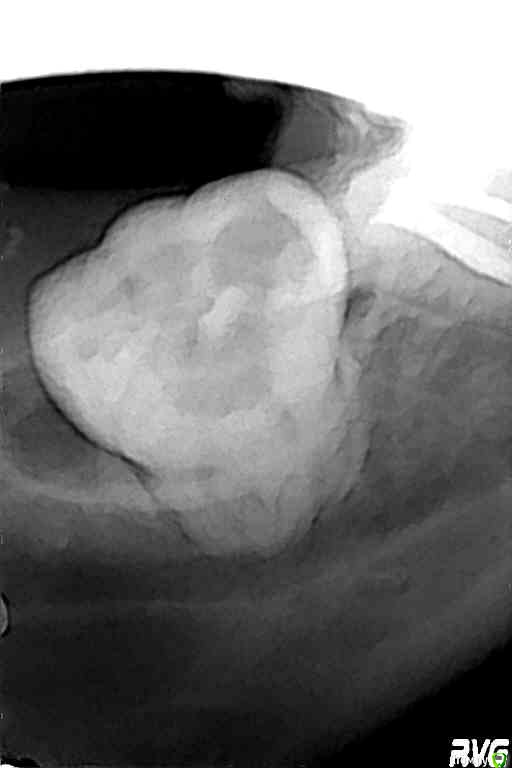

ZubFairy Опубликовано 3 апреля, 2014 Поделиться Опубликовано 3 апреля, 2014 (изменено) Уважаемые доктора,каков Ваш план лечения таких зубов 46,47? Изменено 3 апреля, 2014 пользователем ZubFairy 1 1 Ссылка на комментарий

ZubFairy Опубликовано 3 апреля, 2014 Автор Поделиться Опубликовано 3 апреля, 2014 Фото плохого качества,если получится перефоткаю . Оба зуба не беспокоят.Мой план лечения:перепломбировка каналов в 46,пломба ,коронка . А вот с 47 сложно. На данный момент он пациента не беспокоит,но 2 недели назад были сильные боли на фоне простуды. Сейчас всё ок,перкуссия и пальпация безболезненны. Эндомотора у меня нет,файлы обычные,гутта ассорти,эндометазон.(и так на 250 км.вокруг),поэтому послать к другому доктору не получится. Скажите свой план лечения таких зубов? Ссылка на комментарий

Kolchanov Опубликовано 5 апреля, 2014 Поделиться Опубликовано 5 апреля, 2014 Почему семерку-то все приговорили? Что там с ней? По этим снимкам вообще ничего нельзя сказать Ссылка на комментарий

ger_berra Опубликовано 5 апреля, 2014 Поделиться Опубликовано 5 апреля, 2014 Почему семерку-то все приговорили? Что там с ней? По этим снимкам вообще ничего нельзя сказатьЯ согласна на счёт качества снимков,но мне не нравки тень в бифуркации в твердых тканях. Ссылка на комментарий